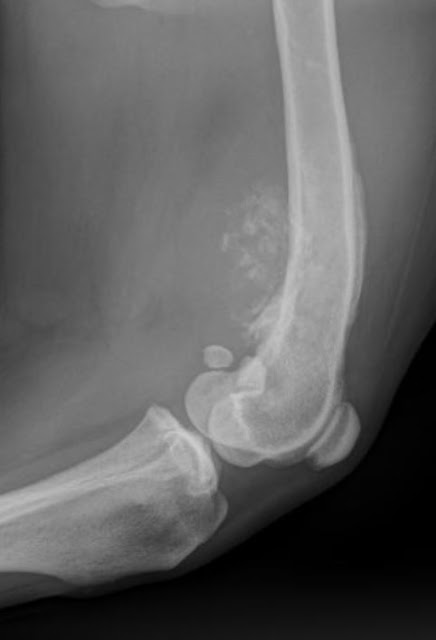

I asked Darby’s owner if I could take an x-ray and he definitely agreed that he wanted one that day. So, off we went. Darby was a wonderful boy in x-ray as he calmly laid on his side for us to take a picture of his leg. What I saw on his picture immediately gave me a pit in my stomach. On the lower part of his femur (bone from the hip to the knee) do you see the swelling of the bone tissue on the right side of the bone and all of the little white spots on the left side of the bone? This was likely bone cancer. With bone cancer, the abnormal tissue will “proliferate” or grow in some areas, but also will “disintegrate” in other areas. Bone cancer is a very painful disease, hence the limp.

I shared my concerns with Darby’s owner back in the x-ray room as I showed him the picture and discussed my findings. His two options were immediate referral for amputation and chemotherapy, or continued monitoring at home with medication to keep him comfortable until it was time for euthanasia. At 11 years old, Darby’s owner chose to keep him comfortable at home until the time came to make a different decision. I felt that was very reasonable given the dog’s age. Many younger dogs can do very very well with amputation and chemotherapy if done early in the course of disease, but it is a personal decision in every case. I also asked Dad to closely monitor Darby for coughing, as bone cancer spreads to the lungs early in the course of the disease. We also discussed rechecking his x-ray every few weeks to see what the bone looked like. Below is his next x-ray from three weeks later. You can see the progression in this short amount of time.